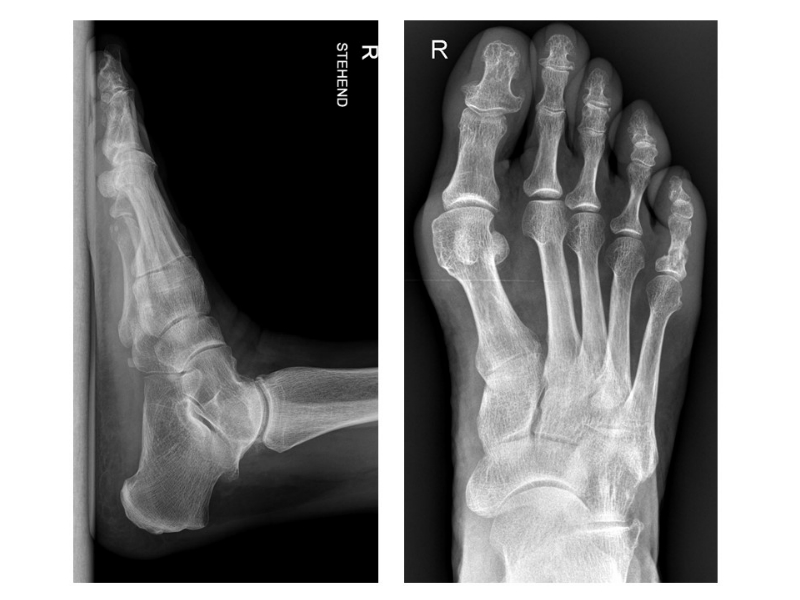

• Röntgenaufnahme des Fußes (unter Belastung) in dorsoplantarem und seitlichen Strahlengang (Abb. 3) und präoperative Fotodokumentation.

Die Akin-Osteotomie erfolgt in mindestens 50% begleitend zu metatarsalen Osteotomien im Rahmen der Korrektur einer Hallux valgus Deformität 12. Diese gehören zu den am häufigsten durchgeführten orthopädischen Eingriffen. Eine präzise Planung der notwendigen Korrektur unter Berücksichtigung aller Komponenten ist daher unabkömmlich. Dabei sollte eine Valgus-Deformität der Grundphalanx mitbehandelt werden, da diese die Entwicklung eines Rezidivs begünstigt. Die valgische Deformität der Grundphalanx mit veränderten Gelenksflächenwinkeln wird als Hallux valgus interphalangeus bezeichnet (Abb. 1). Dabei können verschiedene Winkel zur Definition der Fehlstellung angegeben werden (Abb. 2) 34. Bei der Beurteilung des Hallux valgus interphalangeus im Rahmen einer Hallux valgus Deformität ist zu beachten, daß häufig eine Hyperpronation der Grundphalanx besteht. Durch diese Malrotation werden die eigentlichen pathoanatomischen Winkel "verprojiziert". Am Röntgenbild erscheinen diese projizierten kleiner als die reellen Winkel. Somit sollte intraoperativ nach einer metatarsalen Osteotomie überprüft werden, ob eine Restfehlstellung im Sinne eines Hallus valgus interphalangeus besteht, da das präoperative Röntgenbild die Fehlstellung nicht immer exakt abbildet.